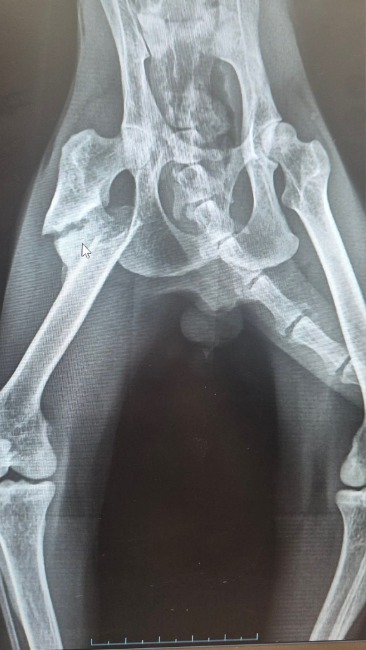

Skwarek nie miał lekkiego życia. Znaleziony pod płotem w jednej z podłódzkich miejscowości przyjechał do lecznicy na zabieg kastracji. Chudzielec z wielką głową, toną pcheł i kleszczy, brudnymi uszami, stanem zapalnym jelit i starym, paskudnym złamaniem łapy, która – bez pomocy lekarza – zaczęła się zrastać po swojemu 😞 W pakiecie ze Skwarkiem dostaliśmy też ogromną ufność i miłość do człowieka… Nie można go było zwrócić ulicy – przyjechał więc do kociarni.

Przed nami cały pakiet działań, by doprowadzić Skwarka do dawno minionej świetności. Z łapką niestety niewiele można już zrobić, to złamanie sprzed 5 tygodni i w tej chwili łamanie łapy od nowa i operacja jej ponownego składania pociągnęłaby ogromne koszty, a jej efekt i tak byłby nieprzewidywalny 😞 Skwarek chodzi, łapkę stawia nieco inaczej niż tę zdrową, ale liczymy na to, że kiedy się już zupełnie zrośnie będzie lepiej. Być może konieczna będzie rehabilitacja ale na razie leczymy stan zapalny jelit, odrobaczamy, karmimy i przygotowujemy się do szczepień. Skwarek zaczyna nowe życie – prosimy – pomóżcie mu w tym starcie. Jest przekochany, przeuroczy i wyjątkowo zadowolony ze zmiany w swoim życiu